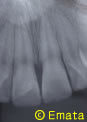

スケートで転倒し前歯を折って来院しました。

歯の神経も露出しています。

折れた歯は持ってこられました

神経もとらず、接着した歯にも問題はありません。小学生だった患者さんは大学生になりました。